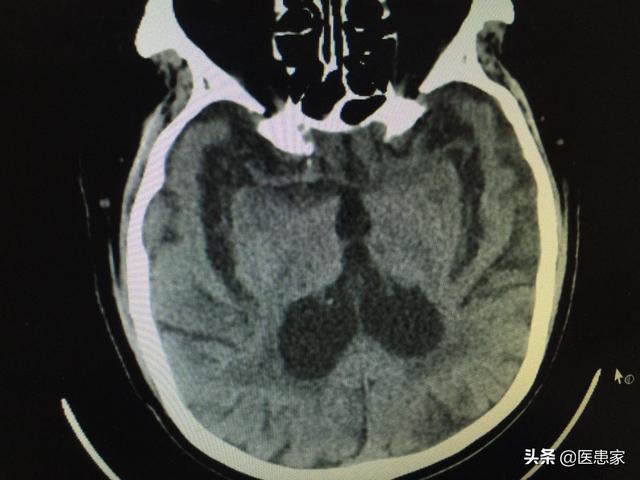

まず脳萎縮≠「アルツハイマー病」(パーキンソン病)である。脳萎縮は別の病気ではなく、客観的な症状、つまりCTなどの画像検査で見られる脳組織の縮小、細胞数の減少、脳室の拡大などの現象で、多くの病気の画像的な現れである。

脳萎縮とは、様々な原因による脳組織自体の器質的な病変により、脳細胞の数や体積が減少し、形態学的に萎縮として現れる現象である。頭蓋CTやMRIでは、脳組織の容積の減少や脳室やクモ膜下腔の拡大が認められることがある。この疾患は50歳以上で発症する傾向があり、数年から数十年続くことがあり、女性よりも男性に多い。

脳萎縮は認知症ではなく、認知症の重症度と脳萎縮は比例しない。脳萎縮とは、脳CTで脳組織の縮小、細胞数の減少、脳室の拡大が認められる現象で、多くの疾患の画像症状である。

脳萎縮は画像診断の一つであり、CTやMRIで灰白質の減少や溝の深化を認めた場合、画像診断医は「脳萎縮」と診断する。病理学的には、脳萎縮は脳組織の縮小、細胞数の減少、脳室とクモ膜下腔の拡大によって特徴づけられる。脳萎縮は必ずしも病的なものとは限らず、通常は生理的脳萎縮と病的脳萎縮がある。